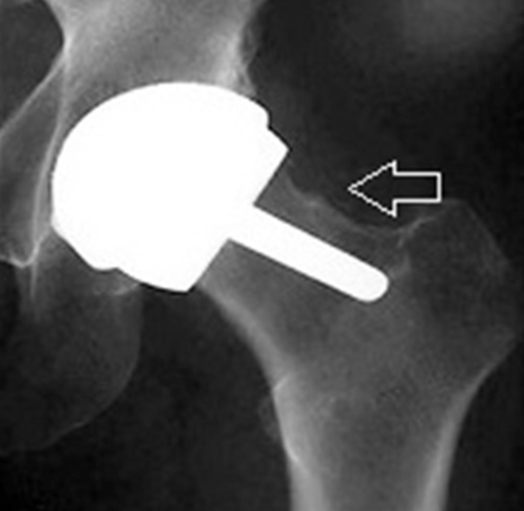

What are the complications of hip resurfacing?